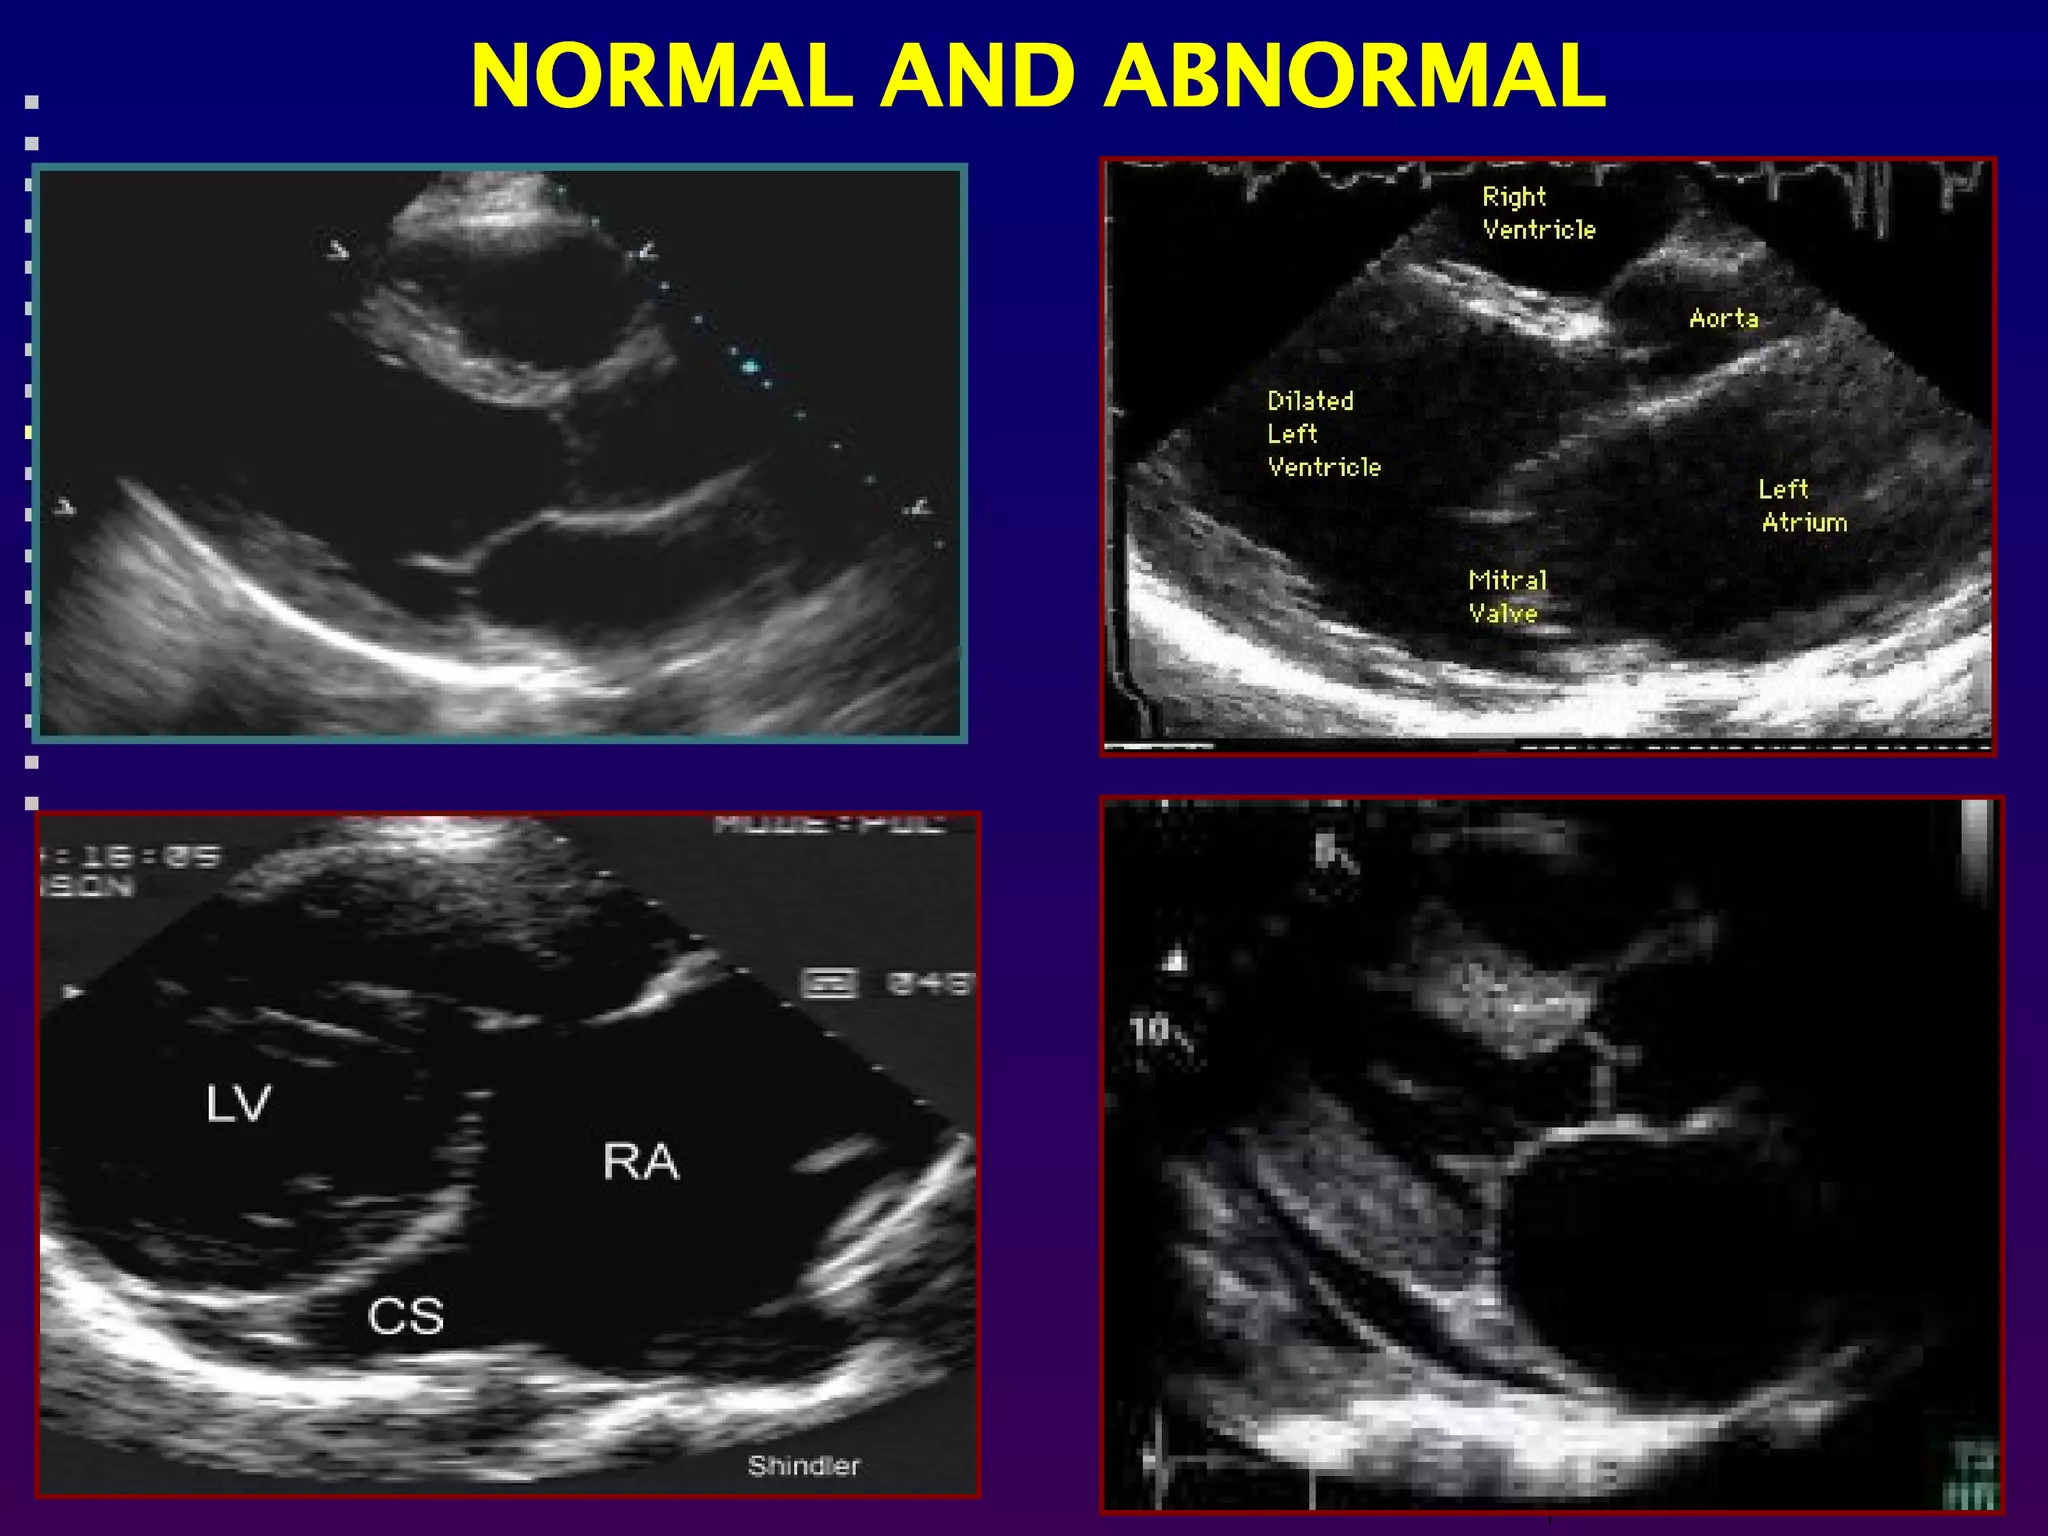

Echocardiography is simply an ultrasound examination of

the heart.During the examination, various different

ultrasound modes or techniques are employed.

-Two dimensional echocardiography allows real time

cross sectional imaging of the heart . This technique

provides most of the information regarding the anatomy,

most measurements of the heart.